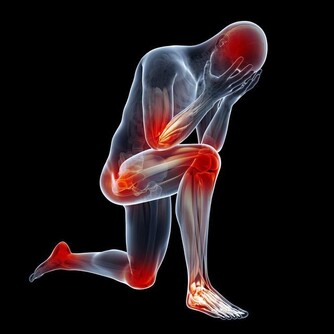

1、多內痔出血

這是一種急性血栓性外痔常見的併發症,出血量多少不定。

2、心臟衰竭

心肺功能不全者,因為便秘可誘發或加重心力衰竭。

3、疝

腹股溝疝,腹壁切口疝和臍疝。

4、心腦血管疾病

高血壓或心臟病,嚴重的便秘,常因排便,腹壓增加,用力過度,精神緊張等因素,誘發或加重冠狀動脈供血不足,血壓暫時升高或突發腦出血,心肌梗死。

5、咯血

肺結核,支氣管擴張導致咯血患者,緊張的胸腔,腹腔壓力突然升高,血管壁破裂,造成大咯血。